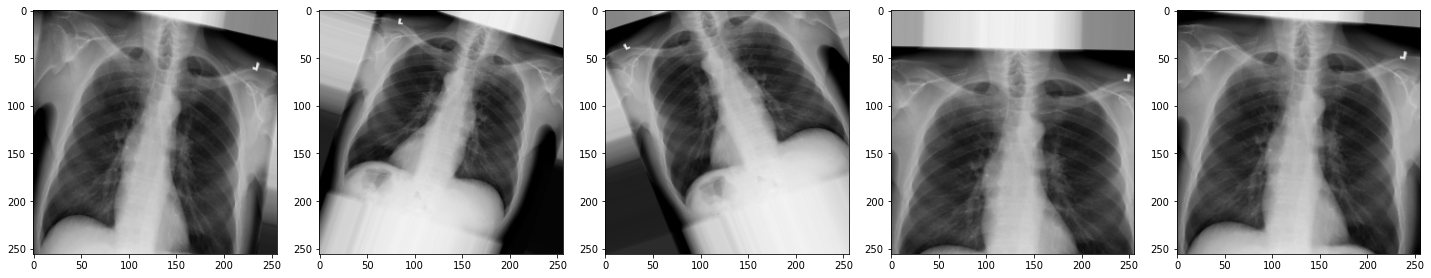

Now let’s view the effect on our X-rays!:

plot_images(augmented_images)

Exercise

- How do the new augmentations affect the appearance of the

X-rays?

Can you still tell they are chest X-rays?

- The augmented images may appear rotated, zoomed, or flipped.

While they might look distorted, they remain visually recognizable as chest X-rays. These augmentations help the model generalize better to real-world variability.

In medical imaging, always consider clinical context. Some transformations, like left-right flipping, could lead to anatomically incorrect inputs if not handled carefully.